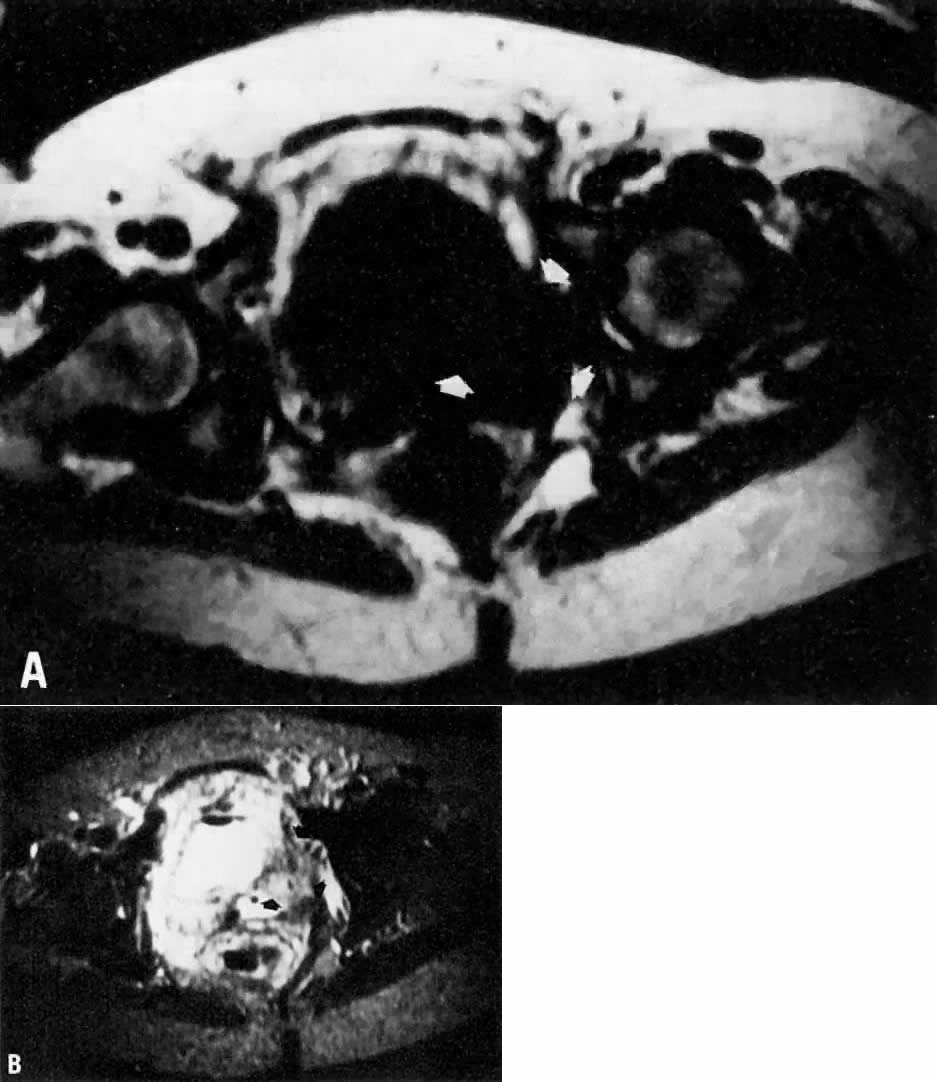

Fig. 8. A. Parametrial extension. Transverse T1-weighted image of a patient with cervical carcinoma extending into the parametrium ( white arrows ). The pelvic side walls ( open arrows) are uninvolved. B. T2-weighted image showing the cancer to have high signal intensity.